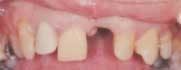

The restoring material of choice was porcelain fused to Captek™ (Figure 2). The health potential of Captek was a major contributing factor in the material selection process. Other attributes of this material reinforcing the decision were the esthetic potential and the ability to predictably bridge Captek units. Due to the subgingival margin placement, cementability of the Captek system was also a plus.

Cases like this are sometimes a mixed blessing for the restoring dentist. Even though the patient's motivation to seek treatment was esthetically based, one must consider utilizing materials that help in the long-term periodontal health. Captek, a unique, internally reinforced composite metal, has a total composition of 88 percent gold and 11 percent palladium/platinum and 2.3 percent silver. Forsyth Research Center (Boston, Mass.) reported that sites restored with Captek composite metal harbored 71 percent less plaque and bacteria in the sulcus as compared to natural healthy tooth structure in the same patients. This research points to the composite metal structure as being responsible for the plaque-resisting potential.